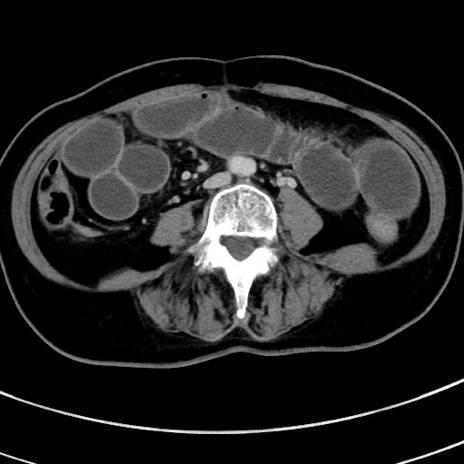

冠状断像